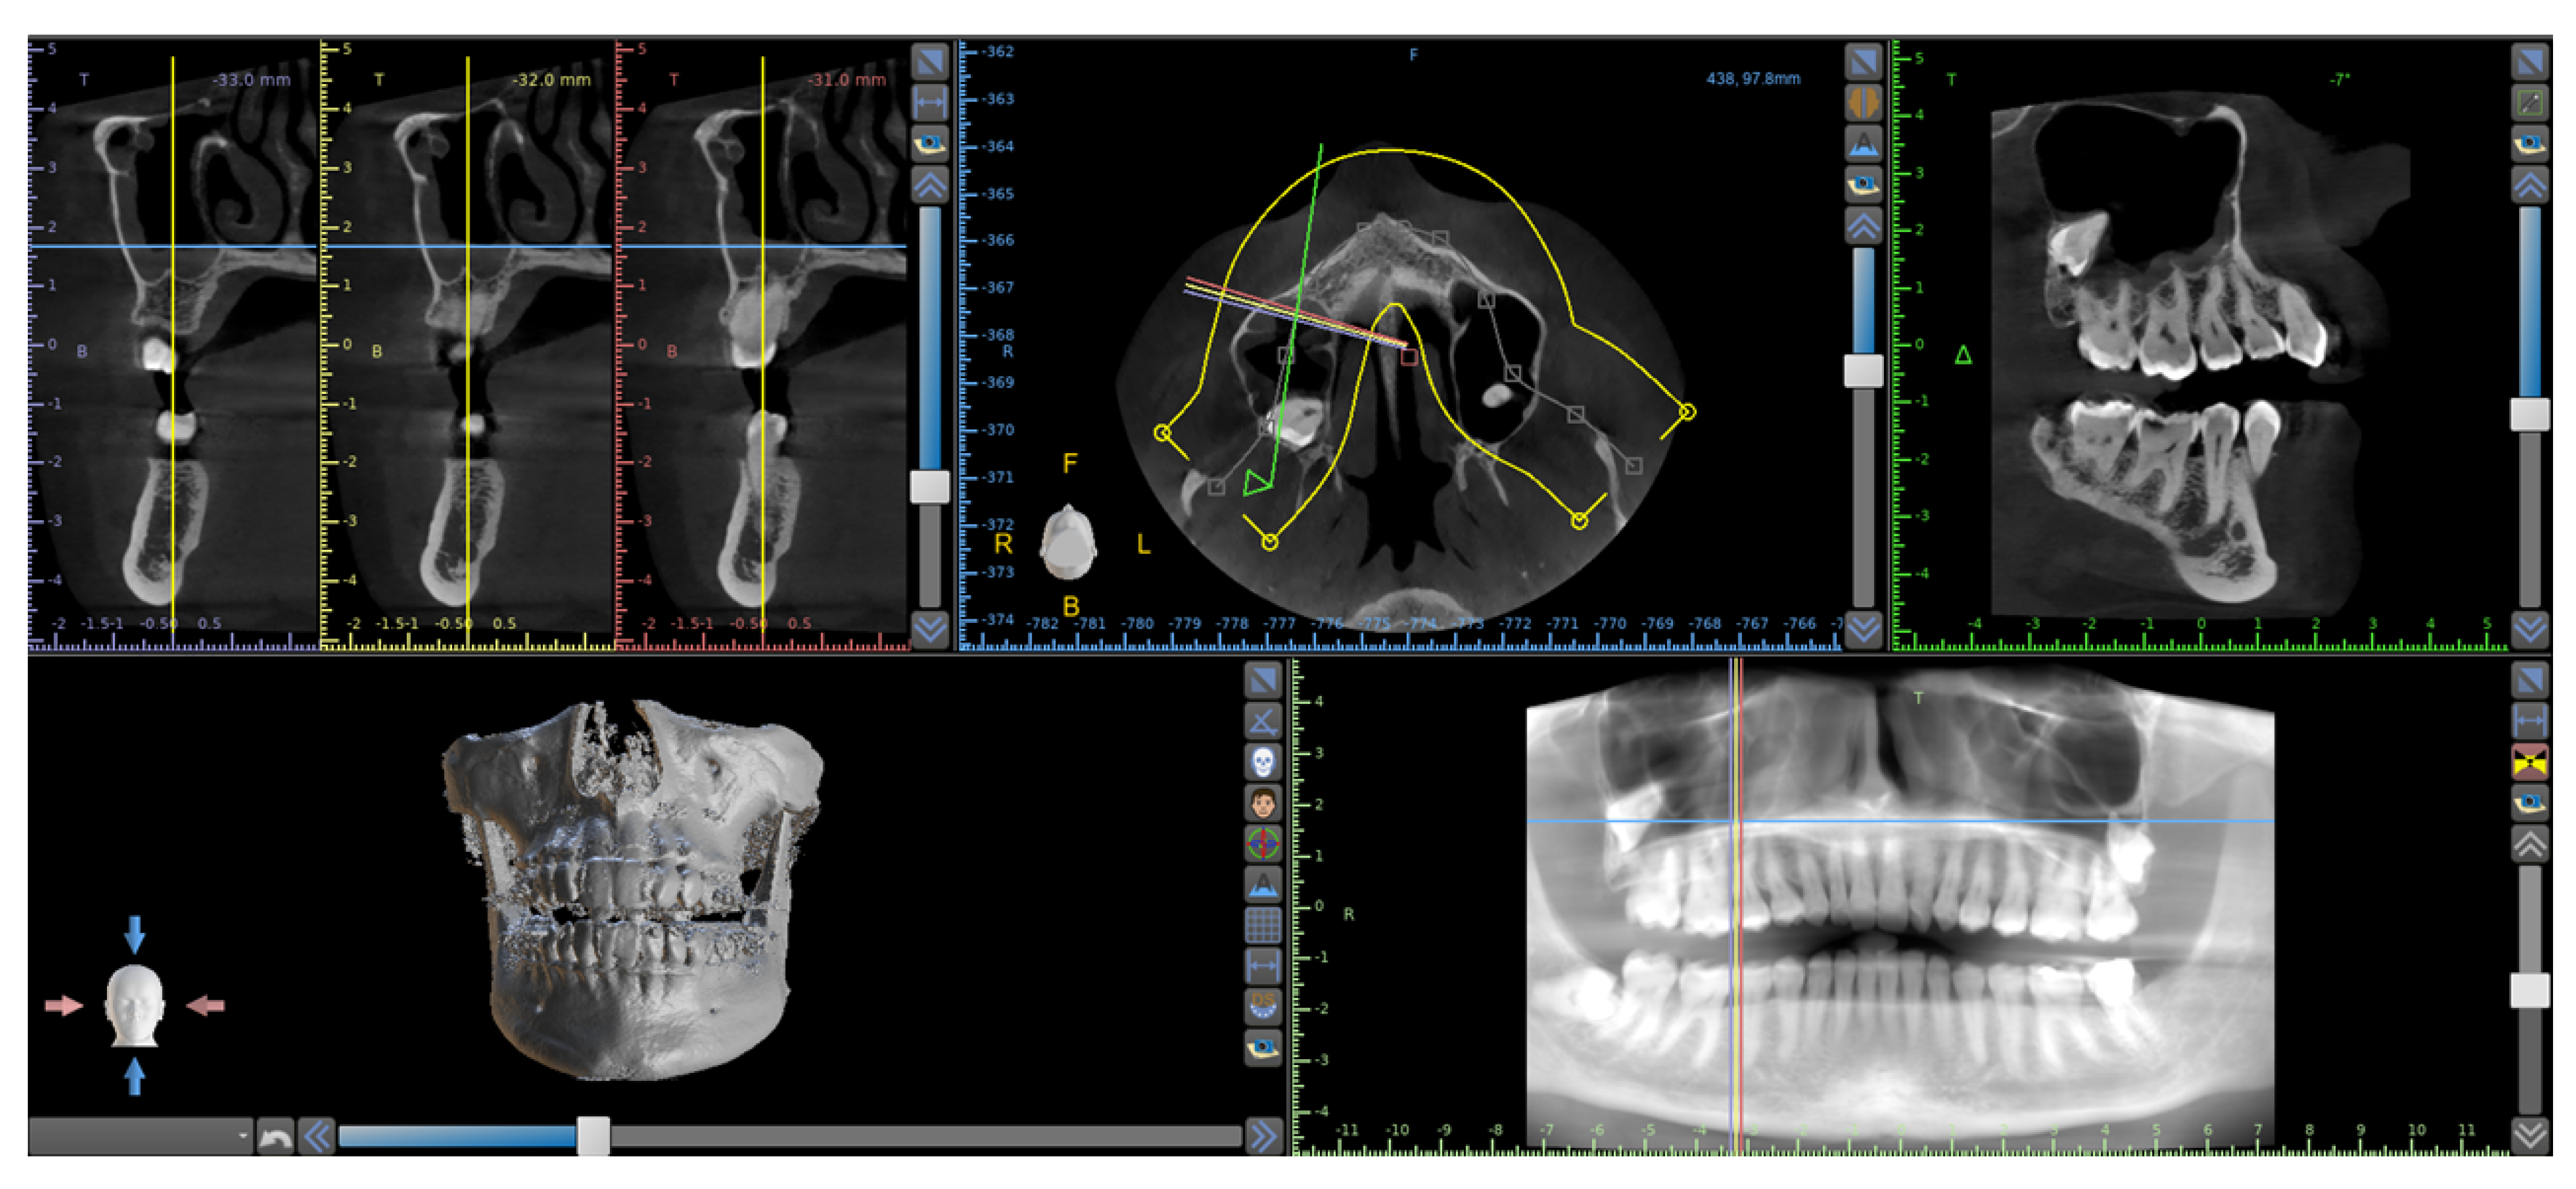

2. Case Report